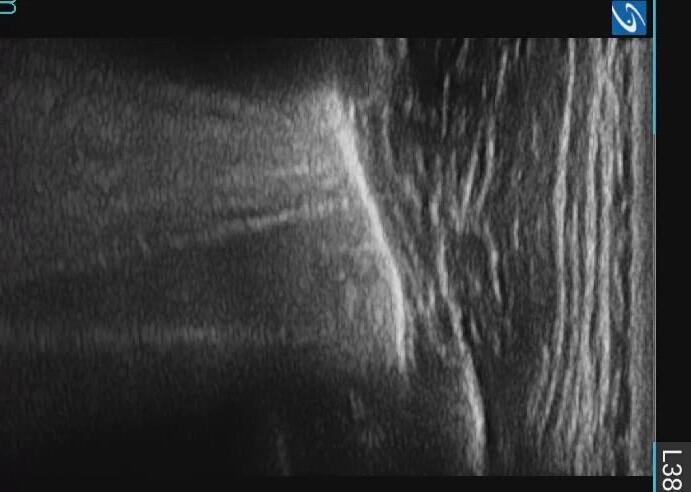

Pediatric COVID-19: MIS-C

Thoracic abnormalities

Cardiovascular abnormalities

Cardiomegaly

CHF or cardiogenic edema

Pulmonary parenchymal abnormalities

Lower lobe atelectasis

Bilateral opacities( ARDS)

Consolidation

Pleural abnormalities

Small pleural effusion

Mediastinal and hilar lymphadenopathy

Abdominal abnormalities

Solid viscera abnormalities

Hepatomegaly

Echogenic kidneys

Splenomegaly

Hollow viscera abnormalities

Gallbladder wall thickening

Bowel wall thickening

Bowel dilation

Gastric distention

Urinary bladder thickening

Peritoneal abnormalities

Small ascites

Mesenteric abnormalities

Mesenteric lymphadenopathy